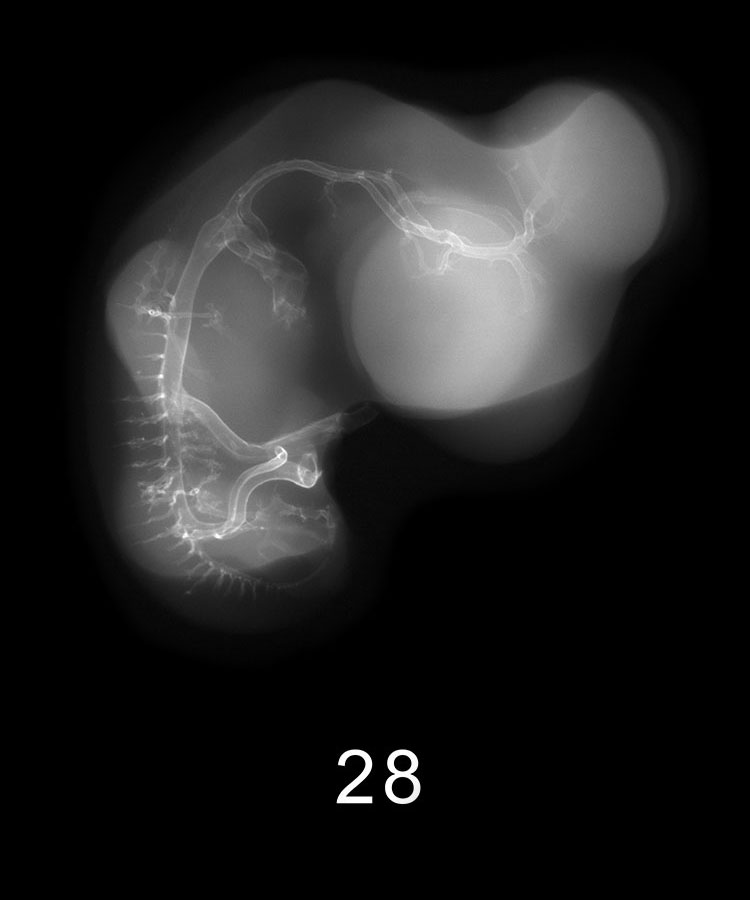

Chick Embryo Microangiography

Images listed by Hamburger-Hamilton (HH) Stage

Hamburger-Hamilton (HH) stages are a system used by those who study chick embryo development to describe the apparent maturity of the developing chick from laying of the egg to hatching. An embryo is assigned an HH stage (numbered from 1 to 46) based on its physical shape and visible features (morphology). This staging system is not dependent on the chronological age nor the size of the embryo, which are susceptible to variations due to breed, temperature during incubation, season, and time between egg laying and incubation. The stages, are in a sense, arbitrary levels of maturity based on multiple physical features. For example, embryos that might have different ages or sizes might be assigned the same HH stage based on their external appearance due to the natural variation which occurs between individuals or due to differing conditions during incubation.